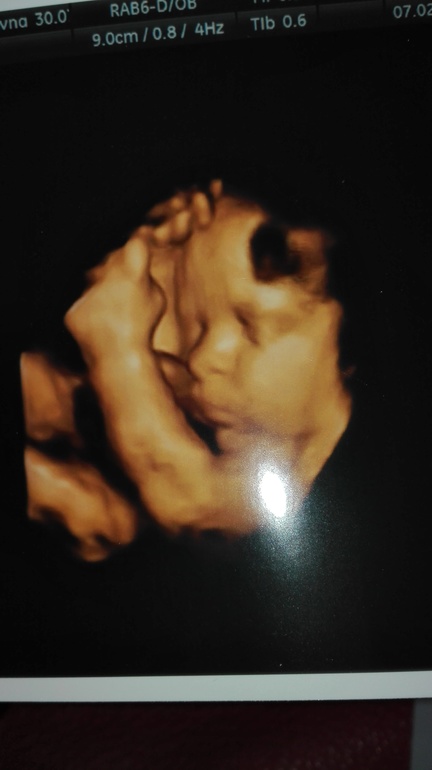

Узи 33 недели ровно

Результаты: УЗИ, КТГ, доплера, скринингаСегодня начинается 34я неделя.

Воды в норме, малыш тоже.

Еще наконец то сказали кто!! Точнее в 12 недель сказали "похоже девочка", сегодня уже точно увидели. Девочка) будет две принцессы

Вес 1800 (по сроку - маленький, но это на столько примерно, что я и не обращаю внимания)

мой пупсик в 33 недели ))) мы на то УЗИ ходили с Настей. И она впервые осознала, что я не просто пузатая )))